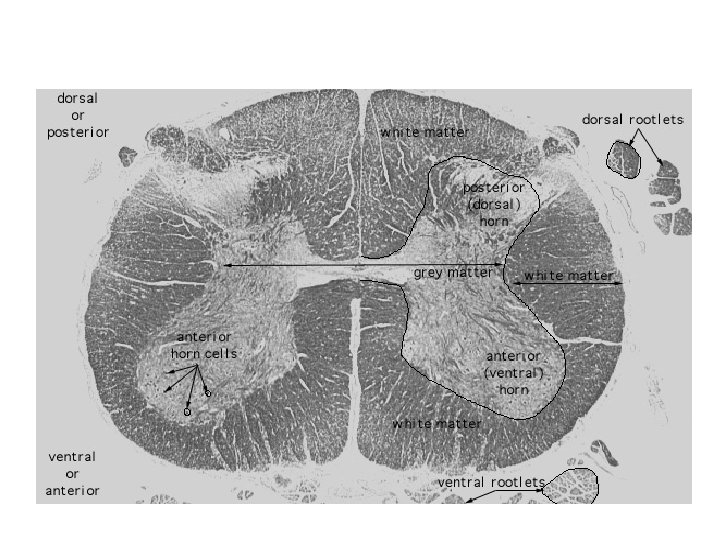

• The spinal cord is organized into two discrete parts. • The outer part contains ascending and descending nerve fibres. • These constitute white matter of the cord. • The inner part contains cell bodies of neurons and nerve fibres. • This is the gray matter of the spinal cord. • Neuroglial cells are in both white matter and gray matter.

• In the spinal cord , the gray matter roughly resembles H shape when in cross section. • Hence the gray matter is said to have two posterior horns and two anterior horns. • In the thoracic part, the cord shows lateral horns on each side as well.

• The white matter surrounds the H shaped region of gray matter. • White matter does not contain any cell bodies of neurons. • The fibers it contains originate from cell bodies lying either in gray matter of the brain or spinal cord or in the spinal ganglion. • The fibers are organized into tracts there are separate motor and sensory tracts.